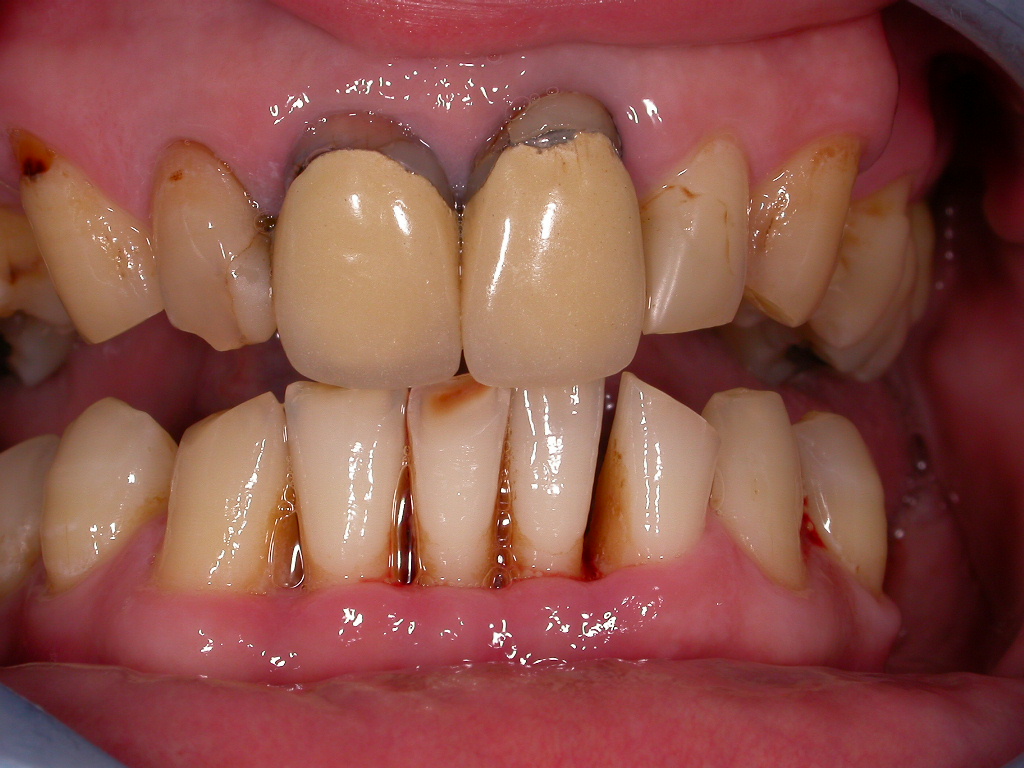

Parodontitis, unschöne Kronen, drohender Zahnverlust

Vorher: Parodontitis, unschöne Kronen, drohender Zahnverlust

Festsitzender Ersatz auf Implantaten

Nachher: Festsitzender Ersatz auf Implantaten